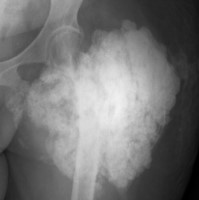

Examination revealed extensive swelling with warmth of the left thigh compared to the right thigh. Radiography of the femur showed large area of tumoral calcinosis overlying left femur. She had a biopsy and partial excision of calcinosis; however, complete excision was not possible because of extensive calcinosis with involvement of femur. Histopathology confirmed the diagnosis of calcinosis. This case highlights the extensive calcinosis associated with systemic sclerosis. Although calcinosis is common in the systemic sclerosis, this degree of extensive calcinosis is uncommon and often challenging to manage. Management usually involves treatment of underlying autoimmune disease. She was on mycophenolate for treatment of systemic sclerosis. There is limited evidence on therapies for calcinosis, hence the optimal management approach is uncertain. She was treated with iv pamidronate and IVIG as adjunct therapy for calcinosis in hospital. She reported significant improvement of swelling and pain in the left thigh, however, was not able to continue pamidronate and IVIG due to insurance issues.

Figure 1: Clinical image.